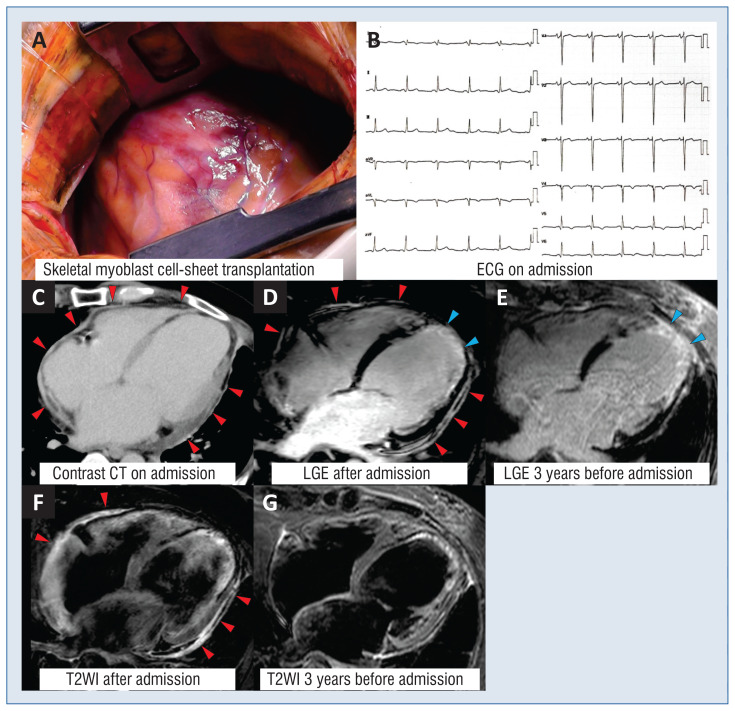

Late-onset pericarditis after autologous myoblast cell-sheet transplantation for ischemic cardiomyopathy.

Ryotaro Matsuo, Tadao Aikawa, Hanako Inoue, Takao Kato, Tohru Minamino